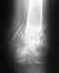

В октябре 2009 г был оскольчатый открытый перелом правой бедренной кости ,после скрепления пластиной и костной пластики перелом не сросся ,осколки кости рассосались и образовался дефект . Далее ,в июне делали повторную оп ,удаляли пластину ,укоротили кость на длину дефекта и ввели гвоздь( с двумя креплениями-вверху и внизу бедра ) ,с которым якобы можно было сразу ходить ...но ходить ,постепенно увеличивая нагрузку, разрешили в конце августа .Все бы ладно ,да только боли в коленке такие ,что наступить в полную силу не возможно .

Покажите хотя бы наиболее свежие рентгенограммы бедра на протяжении.